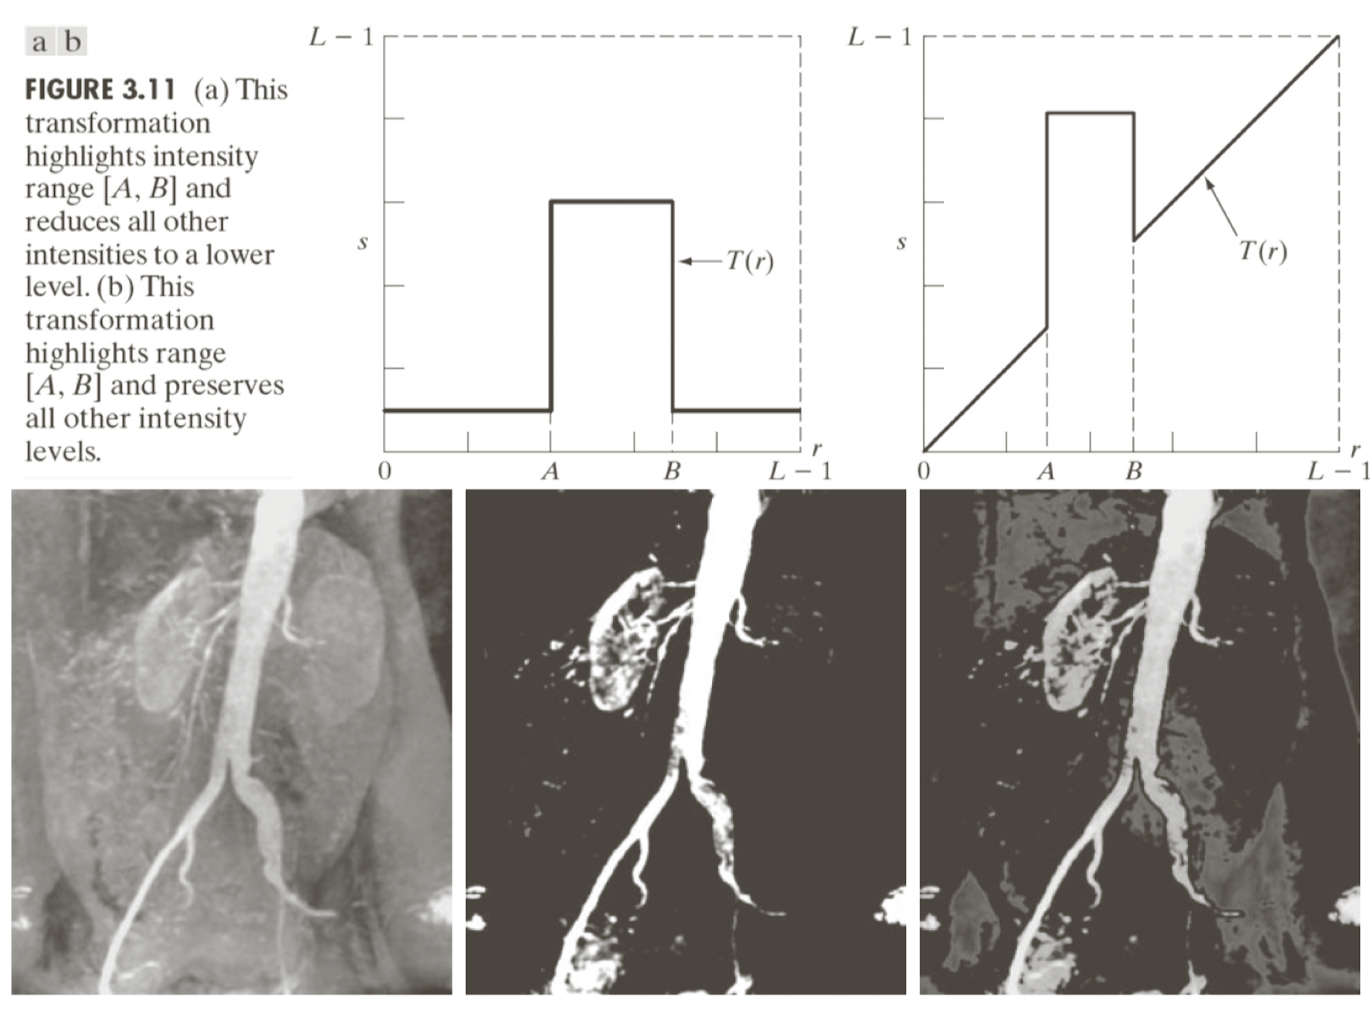

위는 Gray-Level slicing으로 A가 원본일때 B와 같이 강조하고 싶은 부분을 제외하고 전부 검정으로 만들어버릴 수도 있고 C처럼 나머지는 그대로 두고 강조하고 싶은 부분의 값을 늘리는 방식의 filter를 이용할 수도 있다.